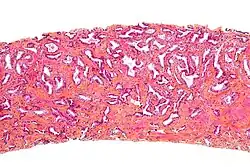

Przekrój przez gruczoł krokowy z widocznym gruczolakorakiem stercza

W około 90–95% przypadków raka gruczołu krokowego u ludzi rozpoznaje się gruczolakoraka zrazikowego[146][147][148]. Rak rozwija się najczęściej obwodowo w części tylnej i tylno-bocznej[148]. Strefa obwodowa jest lokalizacją 68% raków, strefa przejściowa 24%, a centralna 8%[146]. Zwykle (w 85% przypadków) rak jest wieloogniskowy, a jego poszczególne ogniska mogą wykazywać różnice w obrazie histopatologicznym[148][147].

Większość guzów powstaje w strefie obwodowej gruczołu krokowego[151][152]. W 85% przypadków nowotwór jest wieloogniskowy[153]. Makroskopowo guzy są trudne do odróżnienia od otaczającej tkanki, twarde, lite, na przekroju barwy od białoszarej do żółtej[154][152]. Guzy mogą deformować obrys narządu. Typowo guzy widoczne makroskopowo mają tendencję do wyższego stopnia zaawansowania i złośliwości w porównaniu do zmian niewidocznych makroskopowo, które często klinicznie nie były badalne palpacyjne. W obrazie makroskopowym rzadko są obecne obszary krwotoczne lub martwicy[154]. Typowo nowotwór szerzy się poza granicę zasięgu makroskopowego[154].

W obrazie mikroskopowym gruczolakoraki gruczołu krokowego znacznie różnią się stopniem zróżnicowania (złośliwości histologicznej), dając spektrum nowotworów od dobrze zróżnicowanych (o niskiej złośliwości), które trudno odróżnić od prawidłowego utkania gruczołu krokowego do zmian o niskim zróżnicowaniu (o wysokiej złośliwości)[155]. Cechą wspólną dla wszystkich raków stercza jest obecność pojedynczej warstwy jednego typu komórek bez warstwy podstawnej, która jest widoczna w prawidłowych cewkach gruczołowych[156][152].